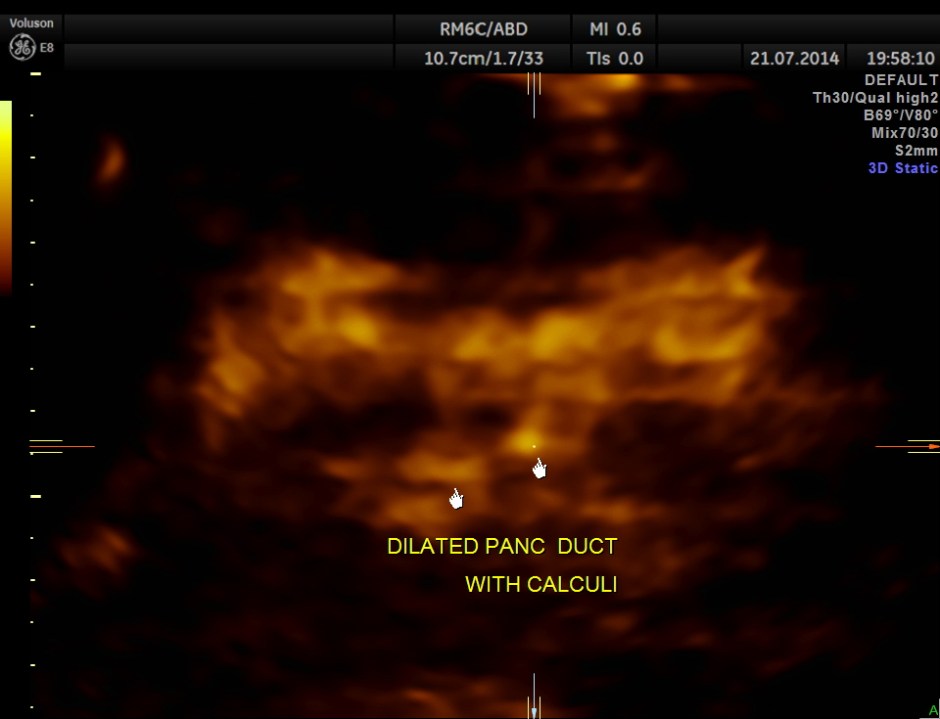

The following pictures show the pancreas.

Pancreatic duct is dilated prominently.

Pancreatic duct dilated.- 12.9 mms.

Pancreatic calculi are seen.

This patient further underwent Upper G.I. endoscopy , which was normal and later MRI scan , which confirmed the ultrasound findings. He was conservatively managed and is clinically better.